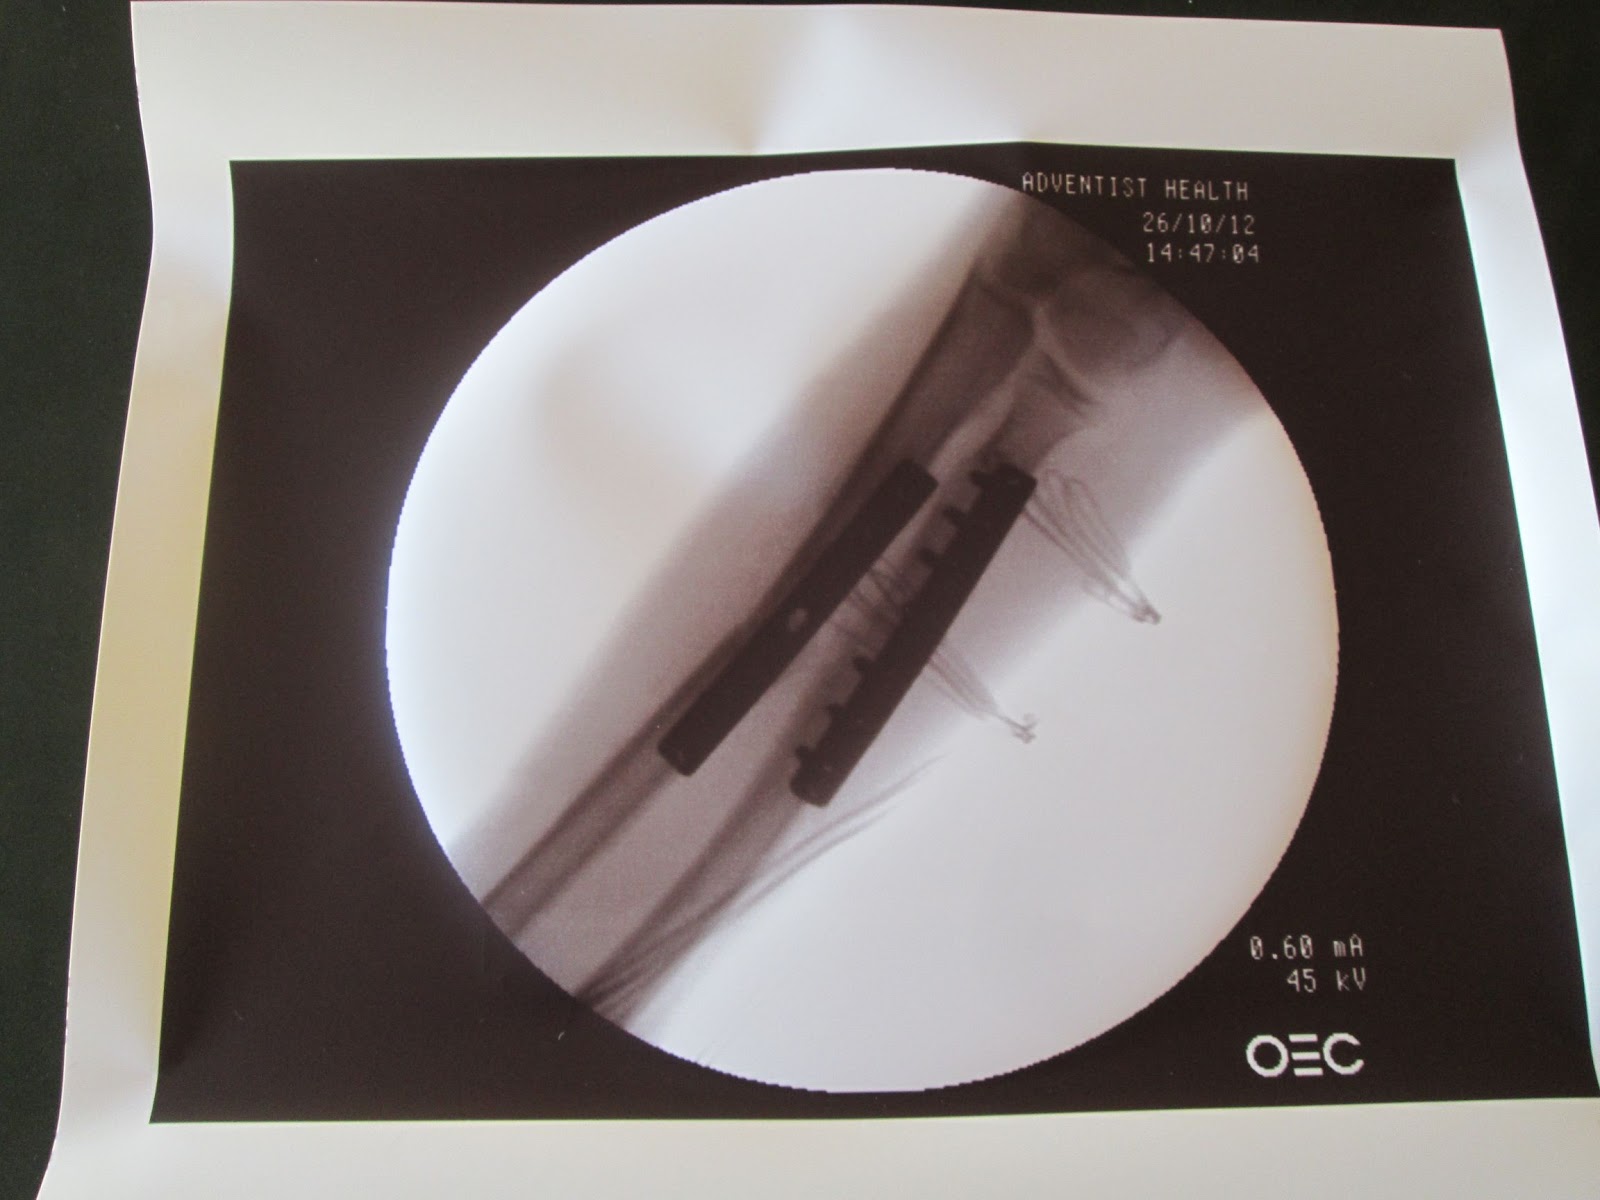

It was great to see how medical personnel continued to work through the storm. Jonathan Delbrice is a boy who broke his arm about 6 weeks ago while he was in the countryside with family. He was one of the first group of people who attended Ed Amos's first medical clinic here at our house. We brought him to Adventist Hospital and xrays were taken of his right lower arm. As shown in this xray both of his lower arm bones were broken. Surgery to reset the bones was made for Thursday.

The hospital came and picked up Jonathan and his mother. His surgery that was originally scheduled for Thursday was done on Friday morning. During the surgery the doctors aligned the bones, put a plate in place and anchored the plate to the bone with pins.